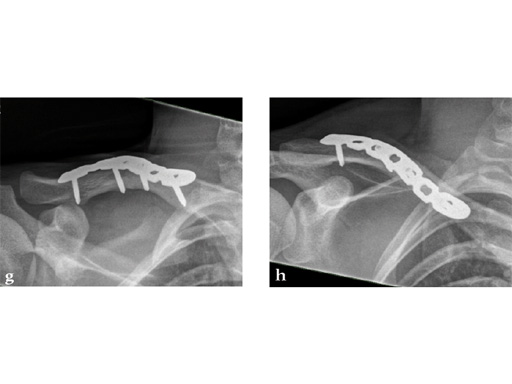

Fig 1 3.5 mm LCP superior clavicle with extension/3.5 mm LCP superior anterior clavicle with extension (short versions of both plates are identical).

Case 2: a 29-year-old man sustained a midshaft clavicle fracture while playing soccer.

Case provided by Norbert Sdkamp and Martin Jaeger, Freiburg, Germany